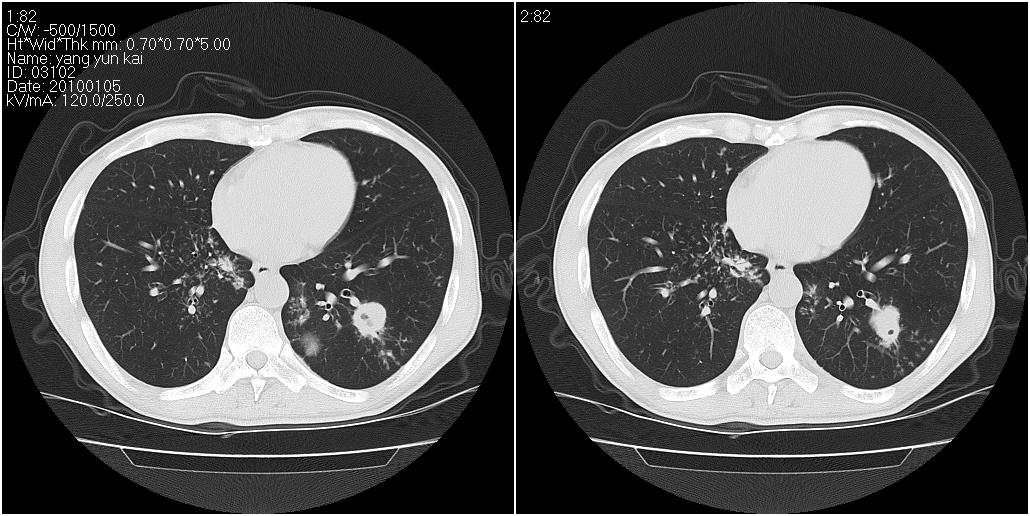

男性,47岁。近来咳痰、咳血,血沉增快(40左右),痰中未检出结核杆菌。

两肺继发性肺结核并多发性结核球形成,部分病灶内空洞形成。

符合继发性结核表现部分空洞形成并播散